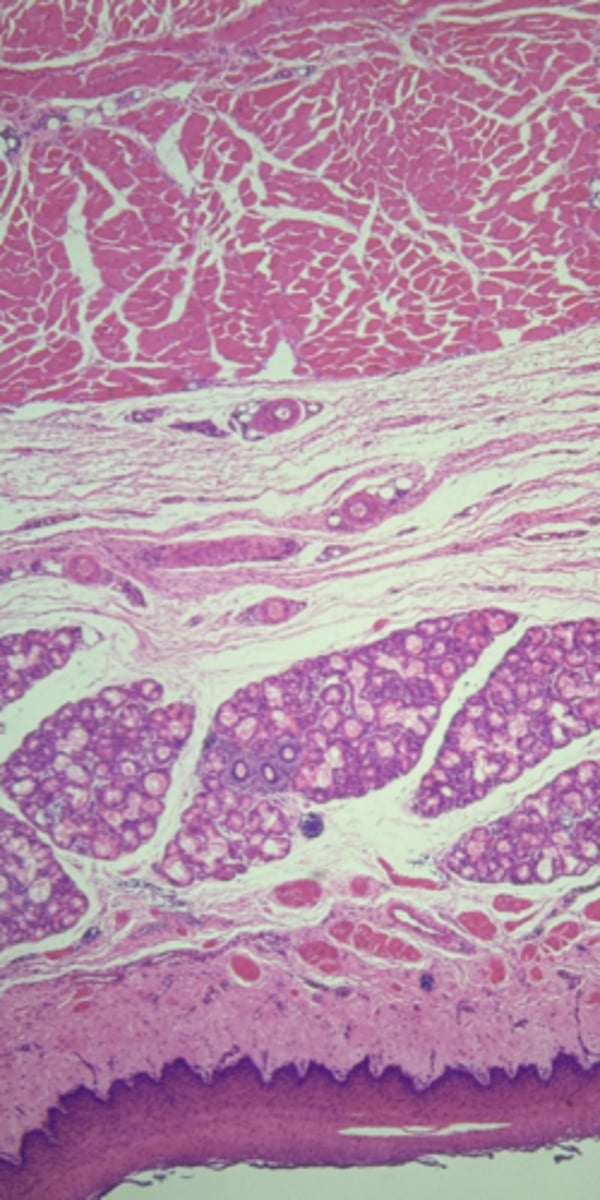

Esophagus

name the tissue

Mucosa

(esophagus)

Submucosa

muscularis externa

A- Esophagus

B- Stomach

Name the Tissue A & B

stomach